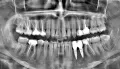

Сделайте рентген-снимок.

Возможно очаг воспаления в области корней передних зубов и стоит проверить, нет ли глубоких отложений в зубодесневых карманах.